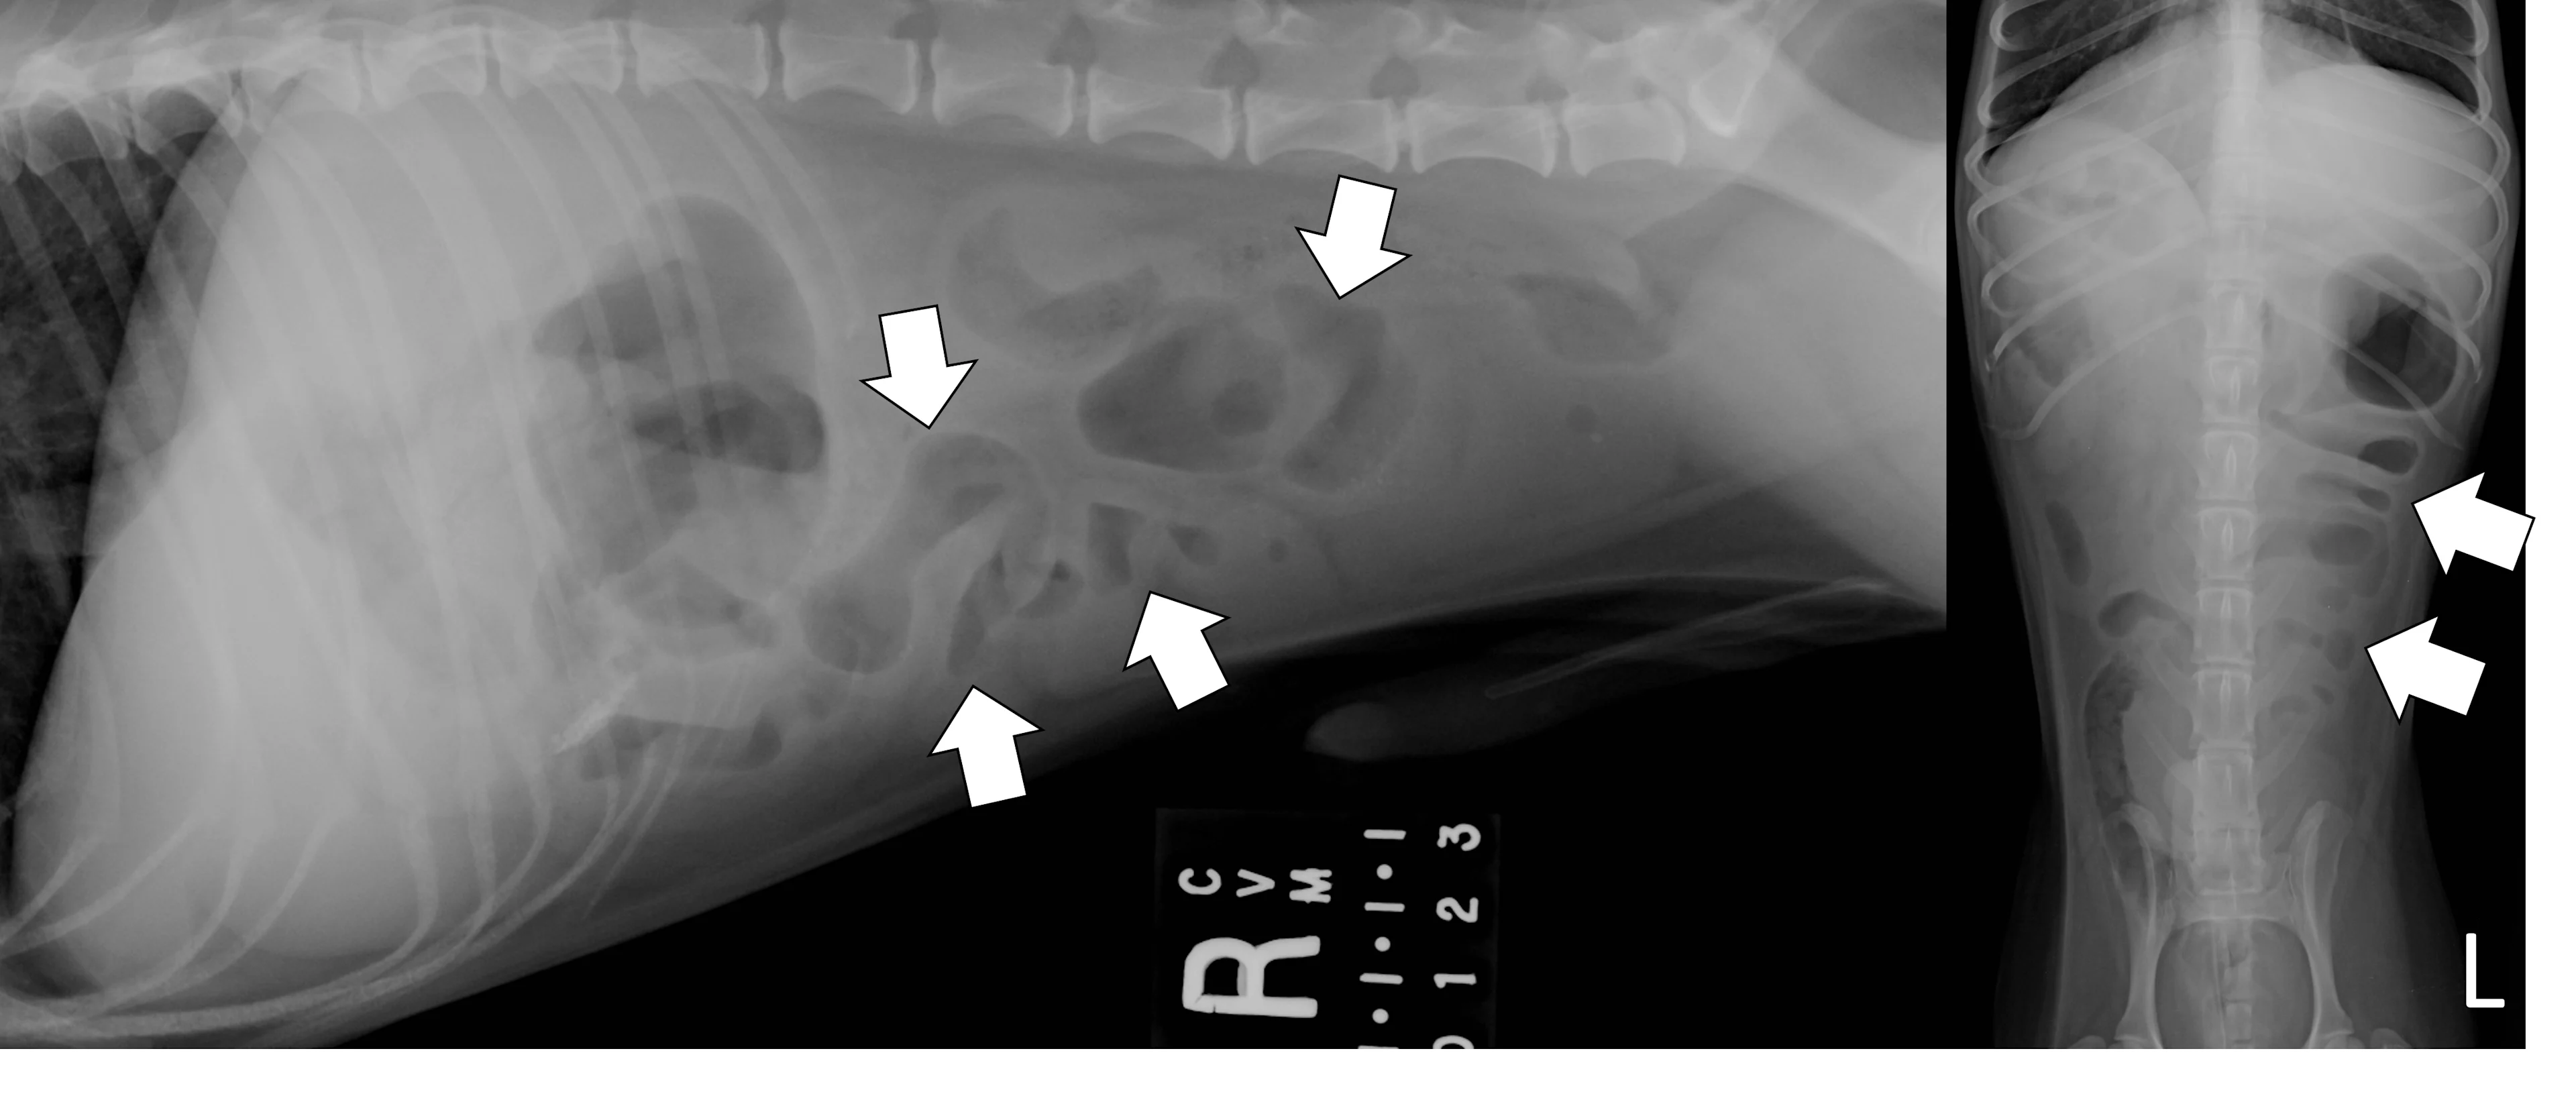

A complete radiographic study includes left lateral, ventrodorsal, and right lateral projections. Obtaining a left lateral projection and performing projections in the aforementioned order can improve visualization of the pylorus and duodenum by shifting gas into the lumens.3 Normal intraluminal gas is an in vivo negative contrast agent that can make soft tissue opaque foreign bodies (eg, cloth) easier to see (Figure 1).

Three-view abdominal radiographs of a 6-year-old spayed dachshund with an acute pyloric outflow obstruction secondary to a surgically confirmed foreign body (cloth). The stomach (pound signs) is moderately dilated with gas and fluid. On the left lateral and ventrodorsal projections, gas outlines an irregularly shaped soft tissue opaque foreign body (arrows) within the pylorus that extends into the duodenum. On the right lateral projection, the foreign body is more difficult to see because it is surrounded by similarly opaque gastric fluid.